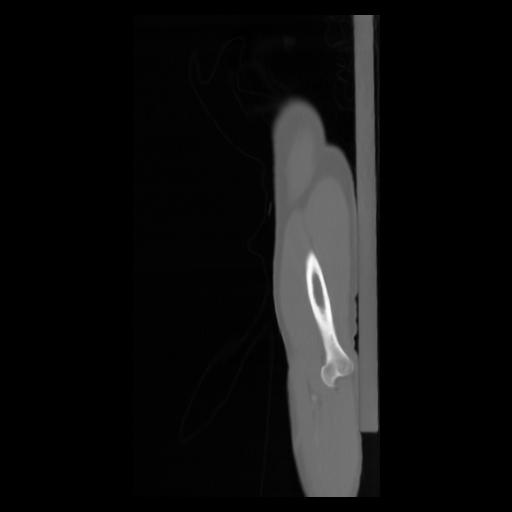

30 CUERPO,CE,Sagittal,3.000,CUERPO,Sagittal,